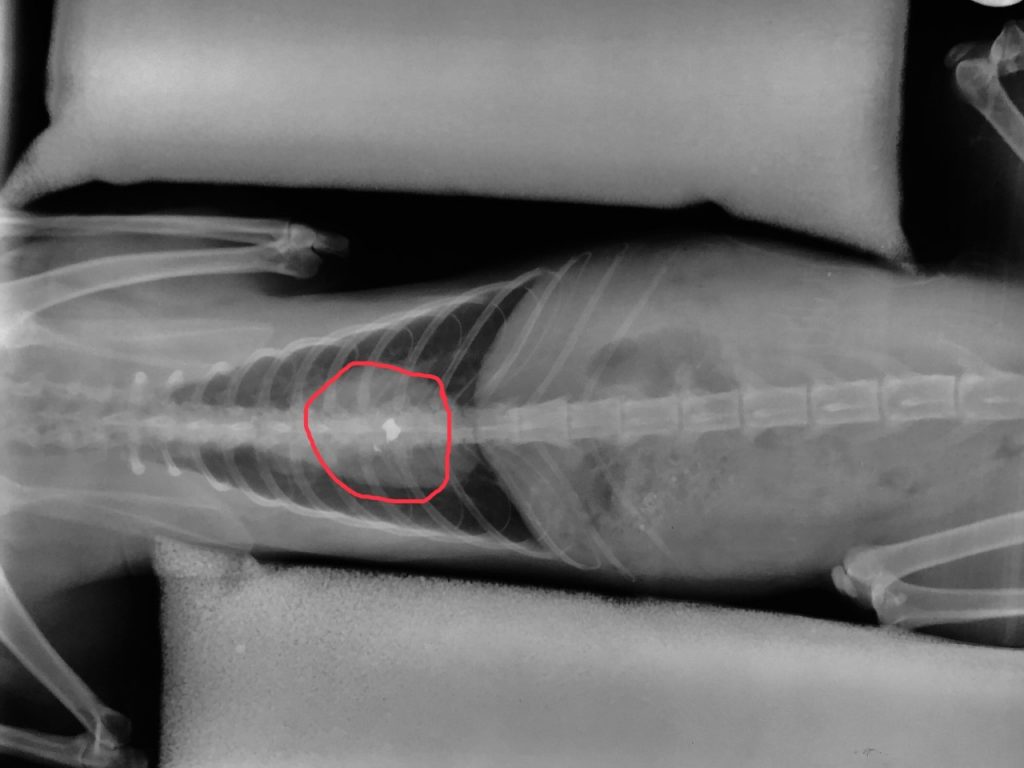

Σύμφωνα με τον αυτόπτη μάρτυρα που κατέθεσε ενώπιον του δικαστηρίου, ο εκπαιδευτικός βγήκε από το σπίτι του κρατώντας αεροβόλο όπλο, σημάδεψε τον γάτο που εκείνη την ώρα ζευγάρωνε και τον πυροβόλησε. Το άτυχο ζώο δέχθηκε τη σφαίρα στην σπονδυλική στήλη, όπως δείχνουν και οι ακτινογραφίες που κατατέθηκαν στο Δικαστήριο. Ο παράλυτος γάτος, φιλοξενήθηκε προσωρινά, στο σπίτι του ανθρώπου που βρέθηκε μπροστά στο συμβάν.

Ο φιλοζωικός σύλλογος απευθύνθηκε σε ιατρείο στην Λάρισα προκειμένου οι κτηνίατροι να αποφανθούν για την κατάσταση του γατούλη αλλά και το πως θα μπορούσε να αφαιρεθεί η σφαίρα που έχει σφηνωθεί στην ραχοκοκαλιά του και μάλιστα είχε βρεθεί άκρη αλλά δυστυχώς το άτυχο ζώο δεν άντεξε.